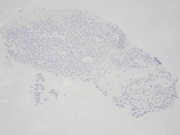

• Figure 6: Cell-block, E-cadherin immunohistochemical stain, 20x magnification

Question 2: Correct answer is C. Malignant

The World Health Organization (WHO) Reporting System for Pancreatobiliary Cytopathology in conjunction with the International Academy of Cytology and the International Agency for Research on Cancer standardized a system for reporting pancreatobiliary cytopathology. This system subdivided diagnoses into seven diagnostic categories (Non-Diagnostic, Benign, Atypical, PaN-Low, PaN-High, Suspicious for Malignancy, Malignant), a distinct departure from the six-tiered system of the predecessor framework, the Papanicolaou Society of Cytopathology System for Reporting Pancreatobiliary Cytopathology (Non-Diagnostic, Negative, Atypical, Neoplastic, Suspicious for Malignancy, Malignant).